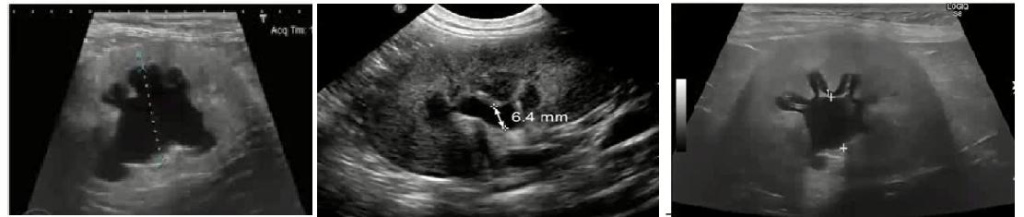

Самая частая ошибка врача ультразвуковой диагностики это неправильное выведение и измерение лоханки (рис 3).

Рис 2. Изображение левой почки (показана треугольниками) собаки мелкой породы при исследовании в продольной (А) и поперечной (В). Почечная лоханка (показана длинной стрелкой) расширена-правильное измерение лоханки.

Рис 3. Как не надо мерить лоханку!

рис 2.jpgРис 2. Изображение левой почки (показана треугольниками) собаки мелкой породы при исследовании в продольной (А) и поперечной (В). Почечная лоханка (показана длинной стрелкой) расширена-правильное измерение лоханки.